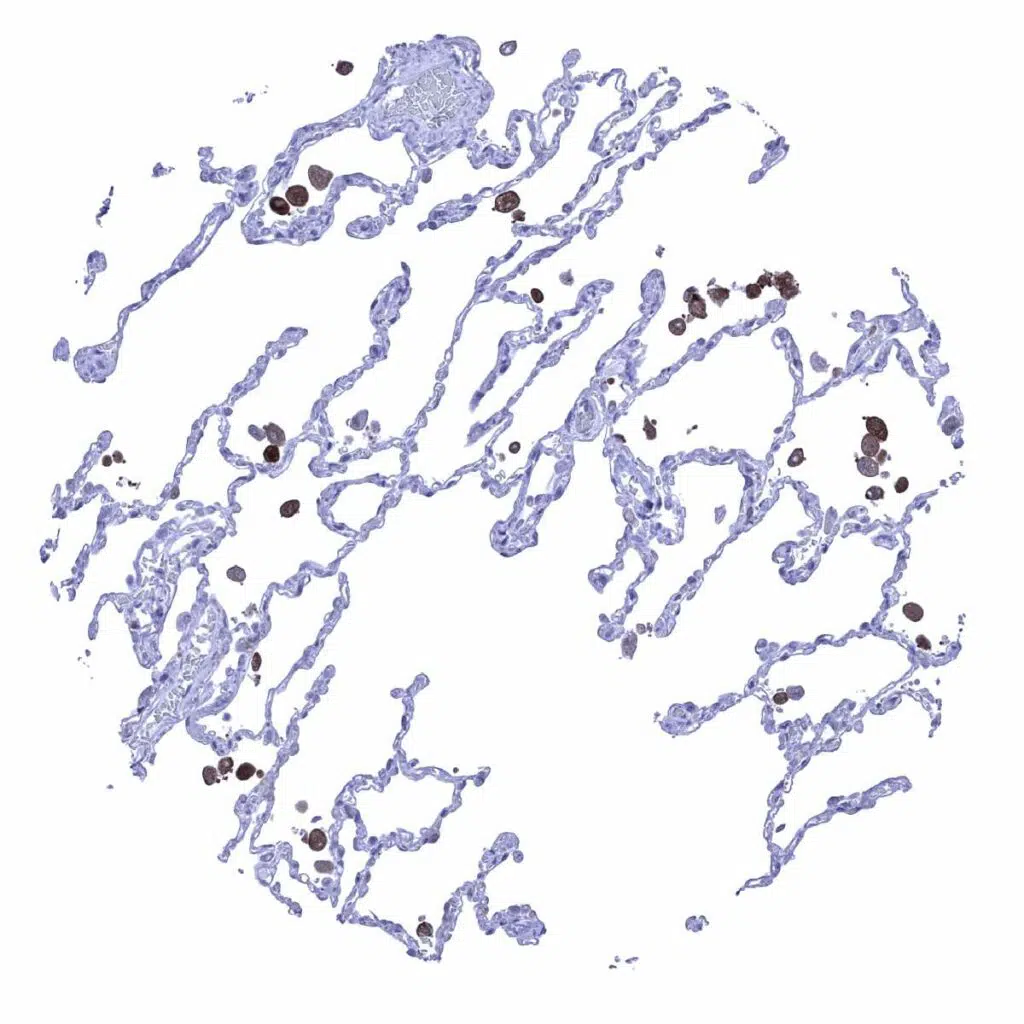

Lung – GS staining is limited to macrophages